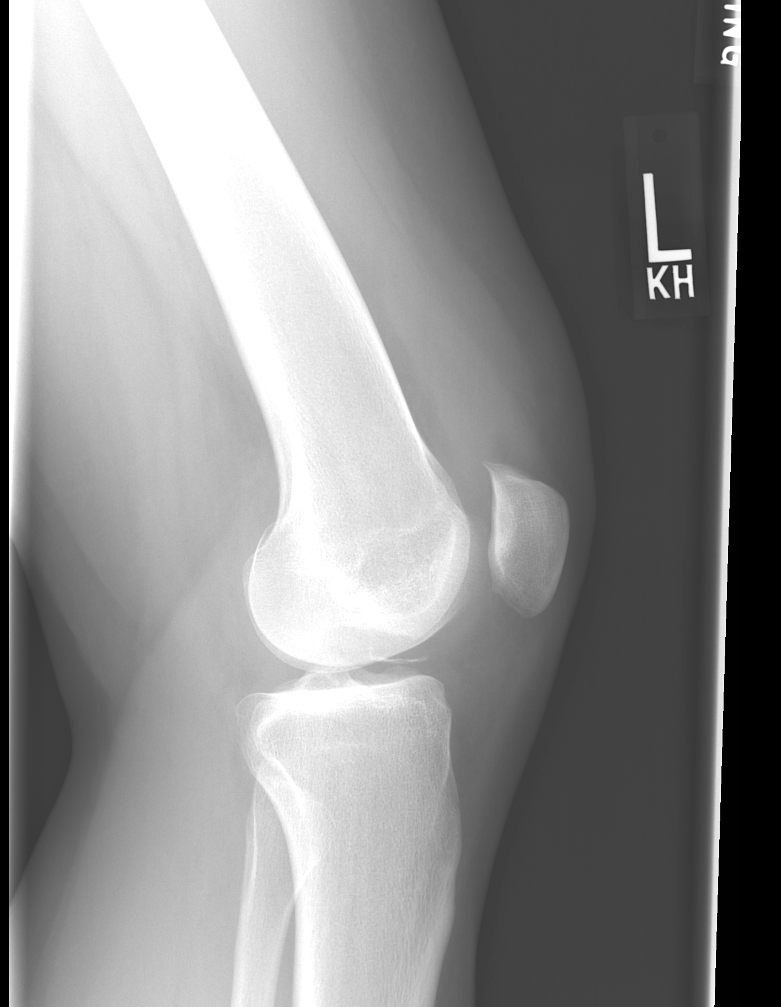

Findings

Bone

Growth plates, ossification centers, apophyses

Joints and alignment